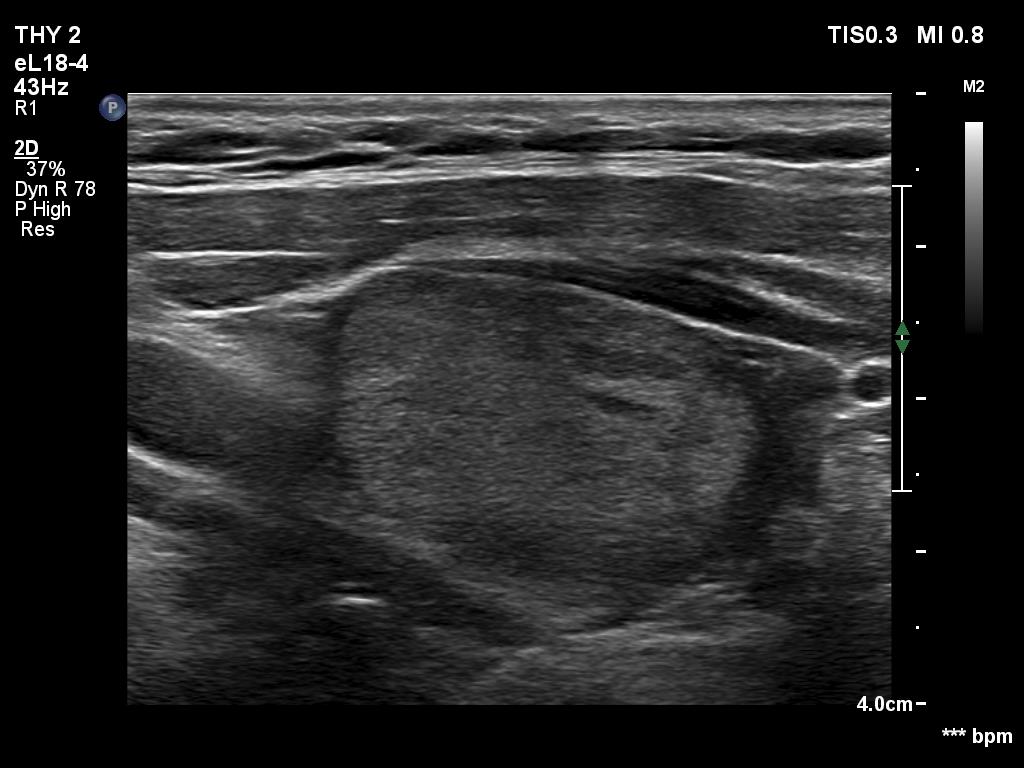

Ultrasonography. The thyroid was hypoechogenic. There was an iso/hyperechoic nodule in both the right and left lobes. The nodule in the left lobe had perinodular vascularity. The dimensions of the nodule in the left lobe were 20x18x31 mm, width, depth, length, respectively. This means that the volume of the nodule has increased almost 8-fold in 10 years.